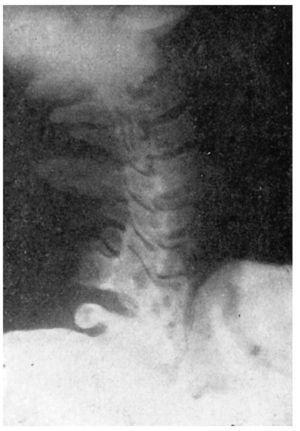

Figura 7 A.Caso núm. 6. M. Y. F. Inestabilidad de la quinta vértebra cervical.

Figura 7 B.Caso núm. 6. M. Y. F. Inestabilidad de la quinta vértebra cervical.

Figura 7 C.Caso núm. 6. M. Y. F. Comprobación a las cuatro semanas de la intervención. Bloque compacto de las 4, 5 y 6a C.